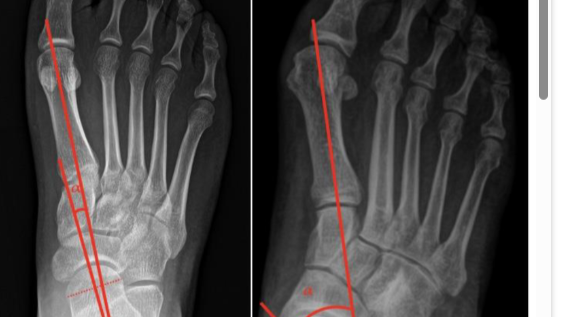

Ramtin has two flat feet. As he grew, it was hoped that special inserts would resolve this issue, but it hasn’t. He walks with pain, and the condition is now also affecting his back.